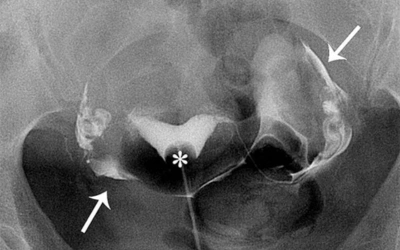

- Hysterosalpingography (HSG) for checking if tubes are open